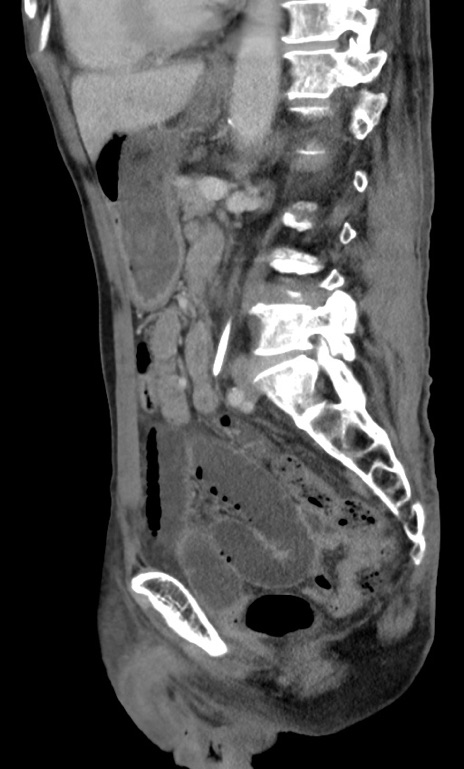

症例3(矢状断像)

【症例】 70歳代男性

【主訴】右鼠径部腫瘤、疼痛

【現病歴】本日朝より上記主訴あり、受診。

【既往歴】膀胱癌にて膀胱全摘、両側尿管皮膚瘻

【データ】WBC 5600、CRP 0.56